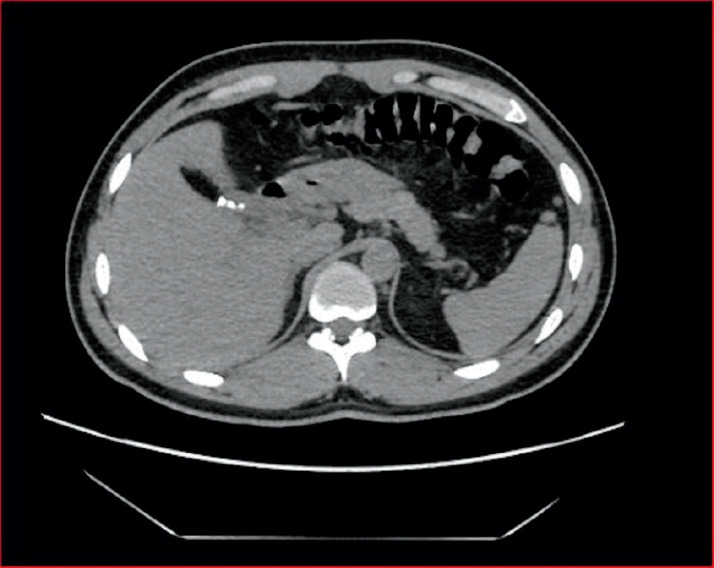

Case presentation: Case 1 is a 31-year-old male who presented with right upper quadrant abdominal pain ten years following SC. Abdominal ultrasound (US) and computed tomography (CT) scan confirmed a ruminant gallbladder. He underwent successful completion of laparoscopic cholecystectomy. Case 2 is a 40-year-old male who was admitted as a case of ascending cholangitis. He had a history of subtotal cholecystectomy one year prior to his presentation. CT scan, Magnetic resonance cholangiography (MRCP), and US all confirmed the presence of a remnant gallbladder. The patient underwent endoscopic retrograde cholangiopancreatography (ERCP), followed by the completion of laparoscopic cholecystectomy.